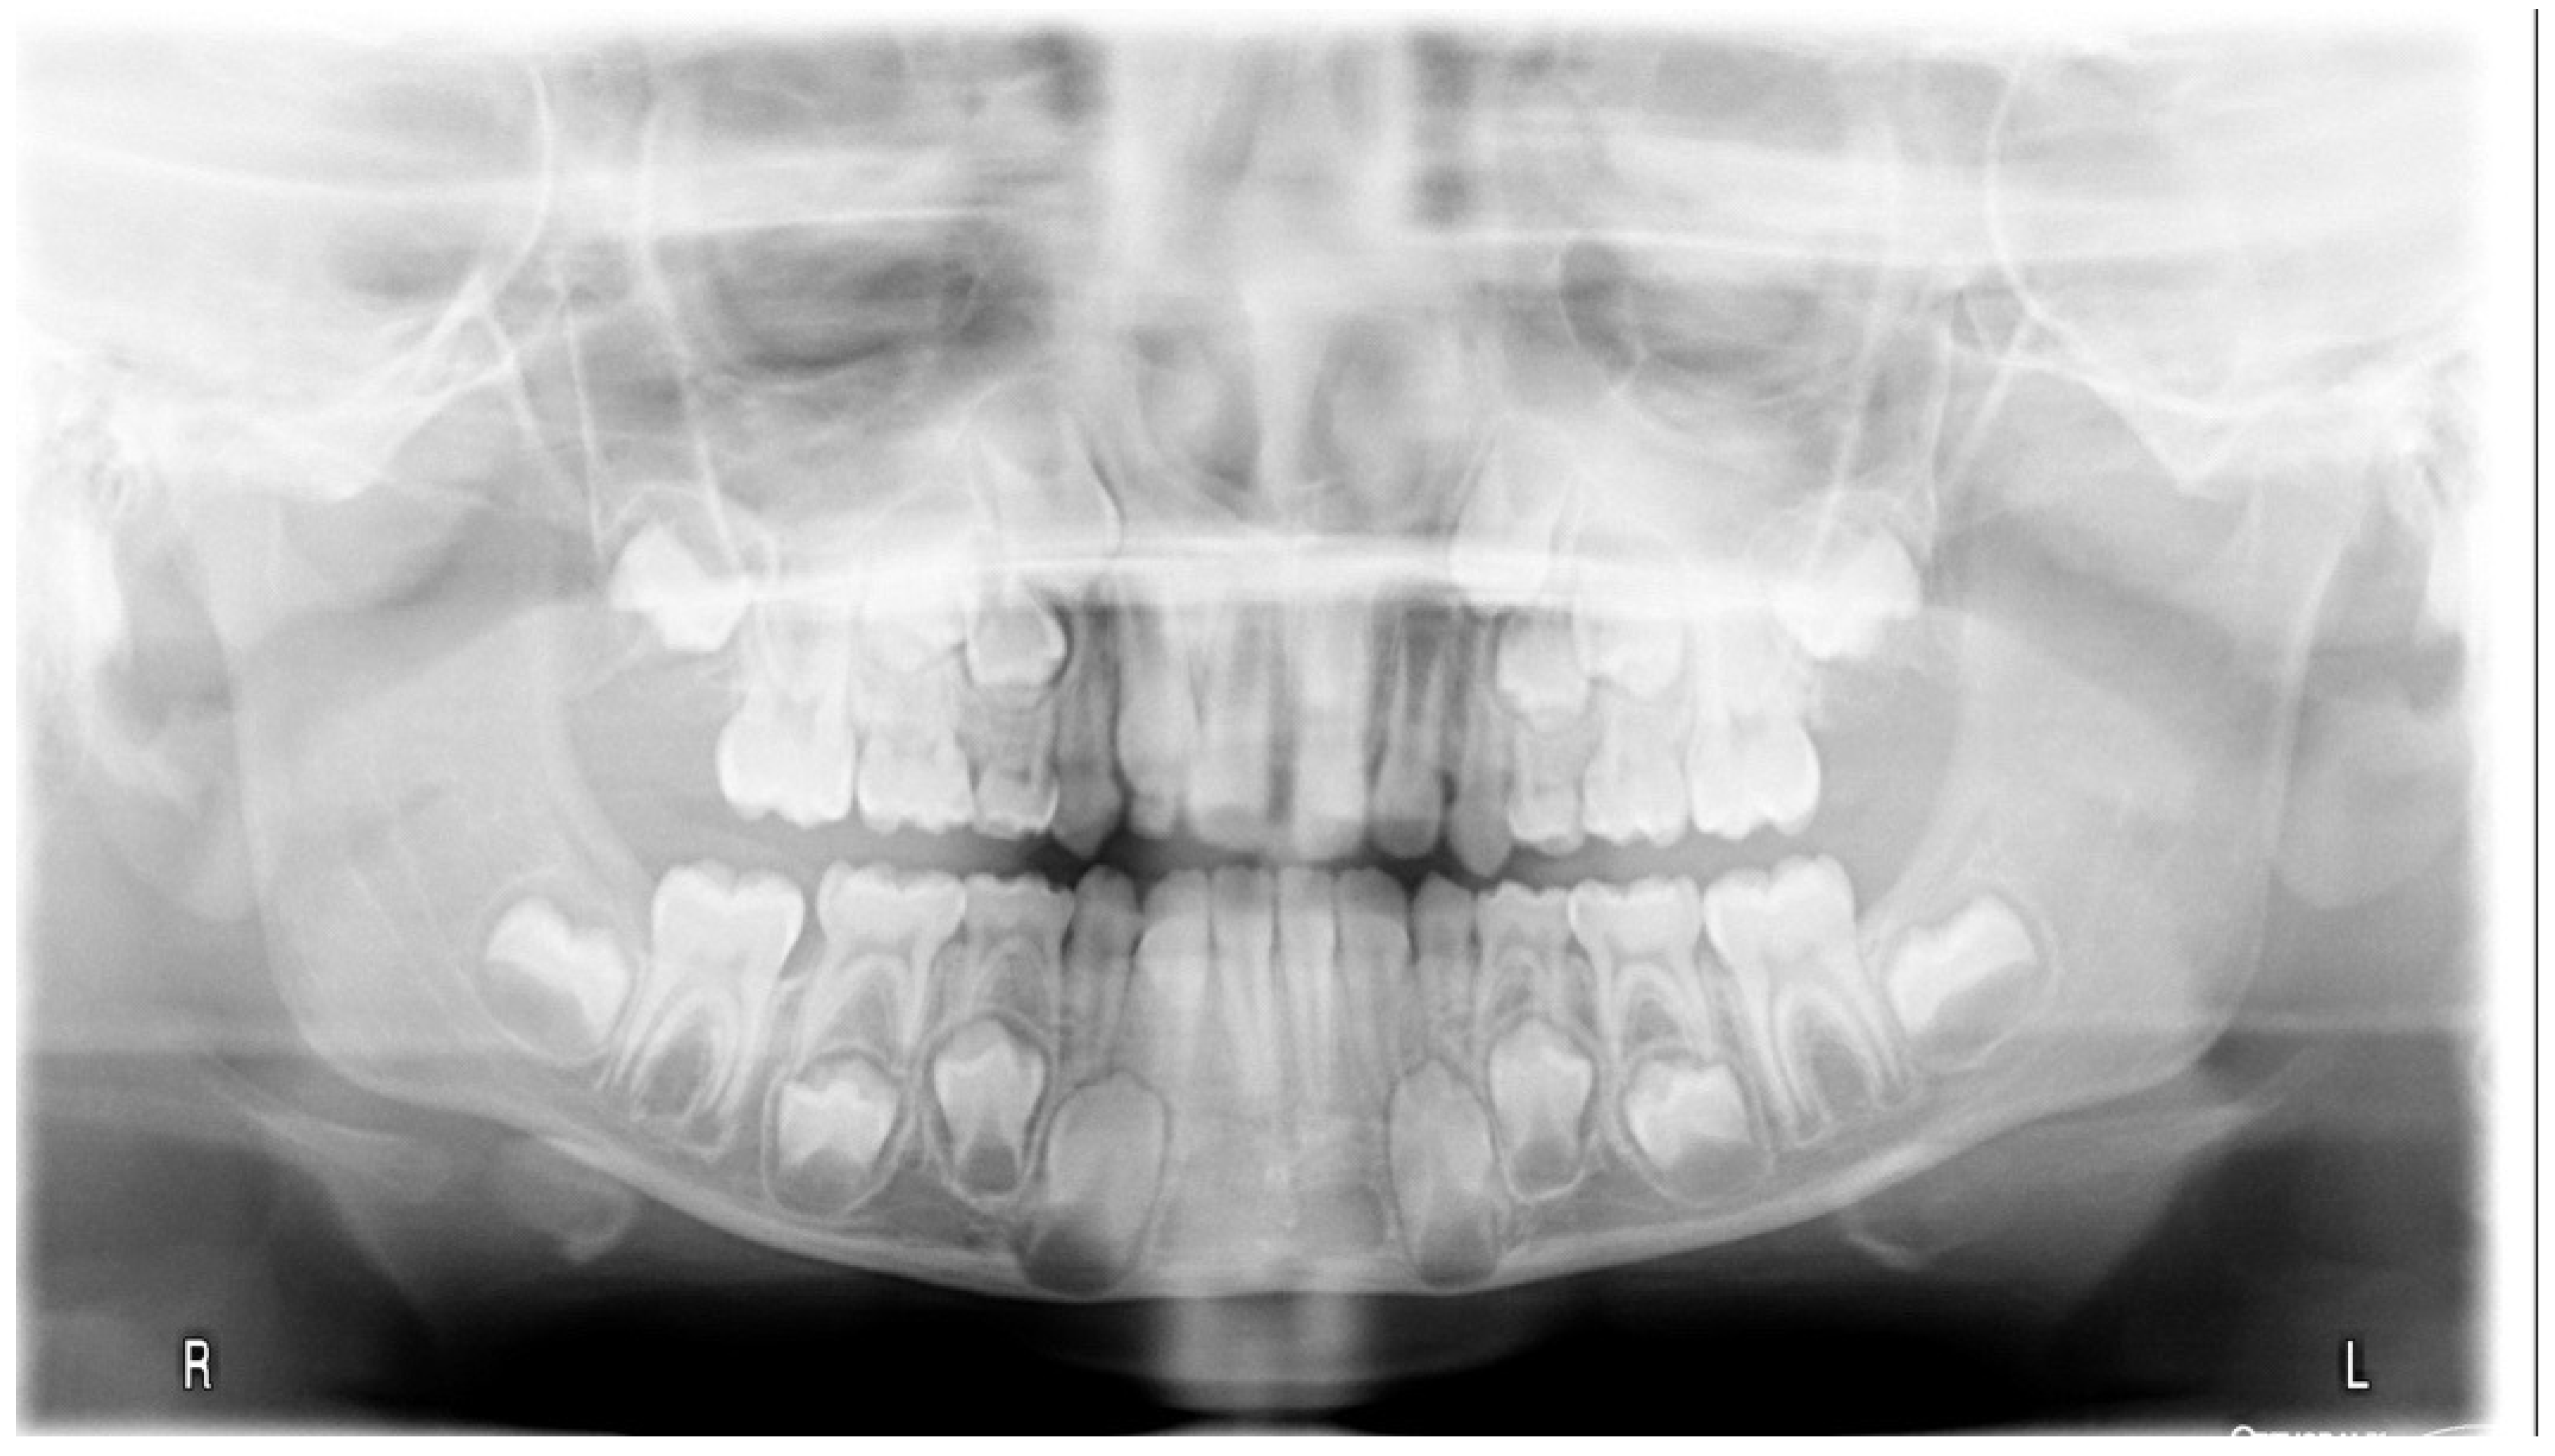

3.1. Clinical Case #1